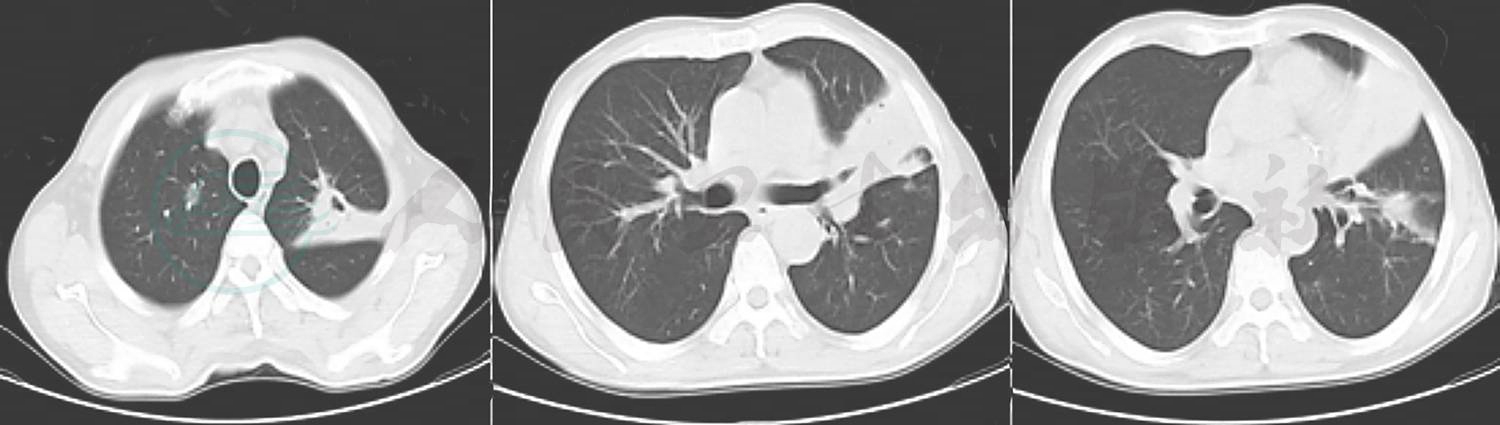

12月29日复查肺CT肺部阴影吸收不明显(图2)。抗感染治疗方案调整为哌拉西林钠他唑巴坦钠、利奈唑胺、两性霉素B雾化及静滴。

图2 2014-12-29胸部CT